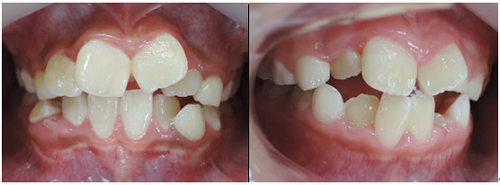

初診時

初診時より1年6カ月後 終了時(10歳9か月)

上下顎骨も拡大でき、咬み合わせの高さも改善できました。

今後、永久歯が萌出してから歯列矯正治療によってさらに美しい咬み合わせに改善していく事となります。